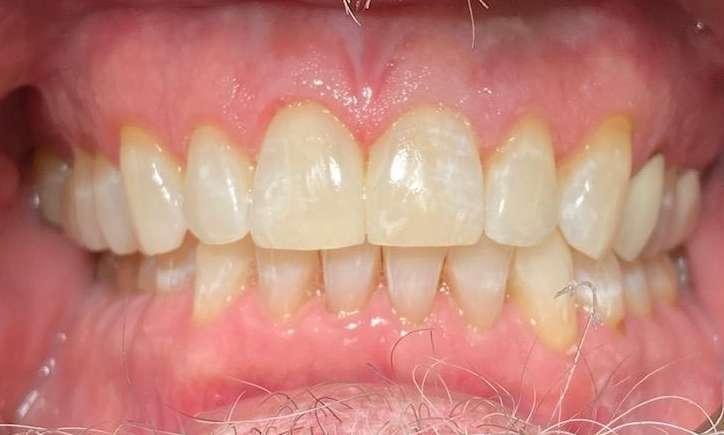

Crowding had caused multiple cracks in this patients teeth. We properly aligned her teeth to protect them from future cracking, filled in the black triangles at the gum line with BioClear and gave her back a confident, healthy smile!